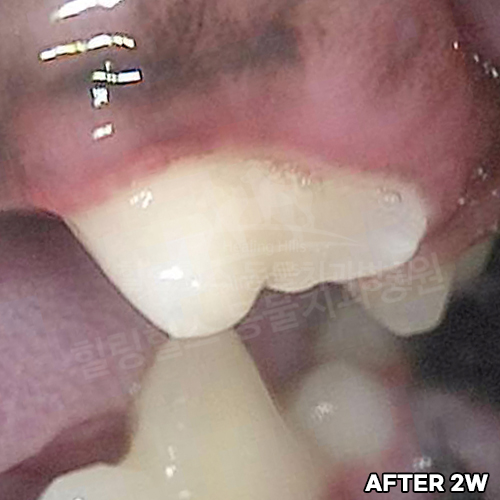

[강아지 치아의 구멍 레진치료 후 2주 경과]